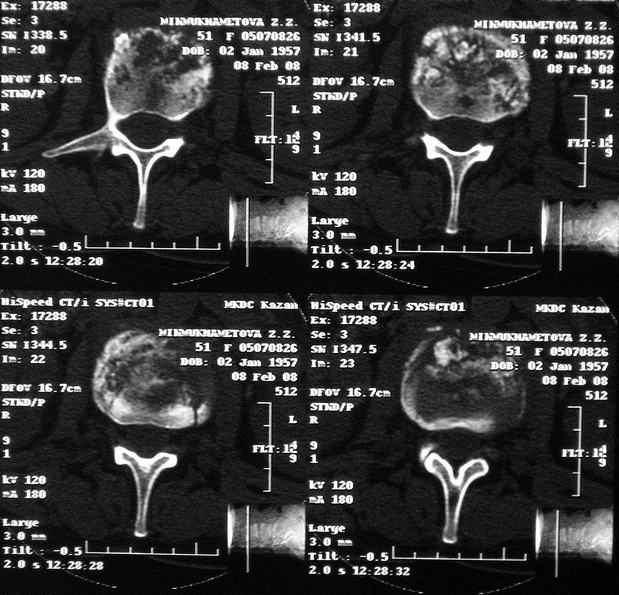

Re: Требуется телеконсультация Вертебролога

послал Коваленко А.Н. 12 Февраль 2008, 22:13

MRI через три недели